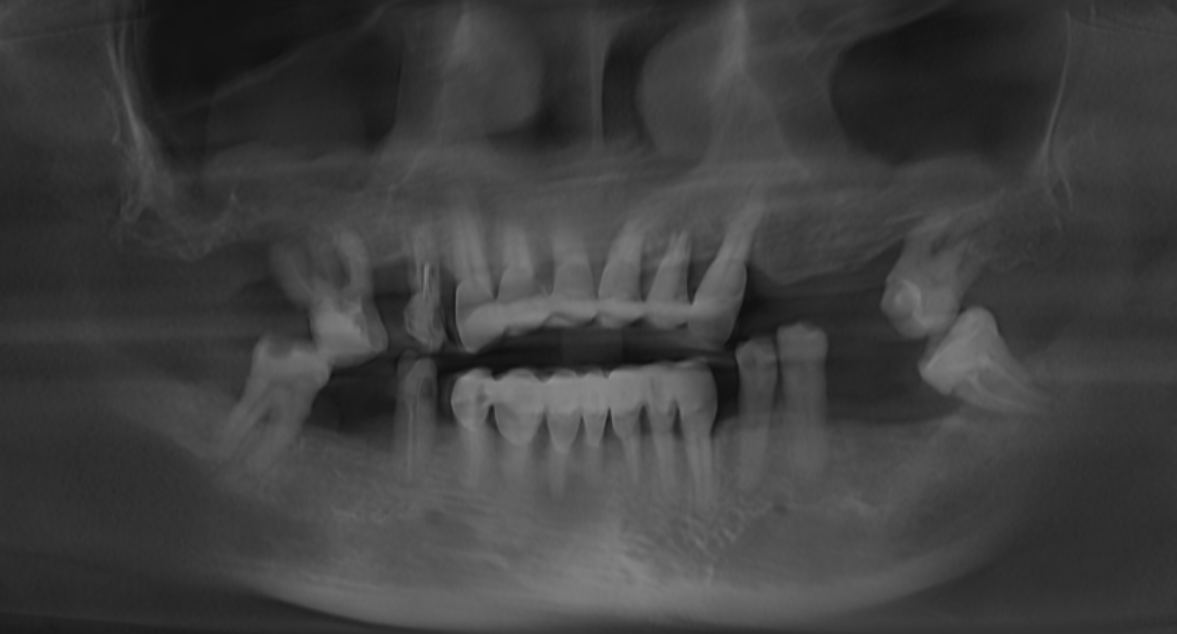

Clinical Situation and Treatment Plan

A 52-year-old female with Type II diabetes presented with failing dentition, characterized by generalized mobility, gingival bleeding, and poorly fitting dentures. Clinical challenges included arch deformities and severe posterior maxillary bone deficiency due to advanced sinus pneumatization. To meet the patient's request for immediate function and esthetics, a "teeth-in-a-day" protocol was implemented, involving full-arch extractions, IPG scanning, immediate implant placement, and the delivery provisional restoration on the day of surgery.